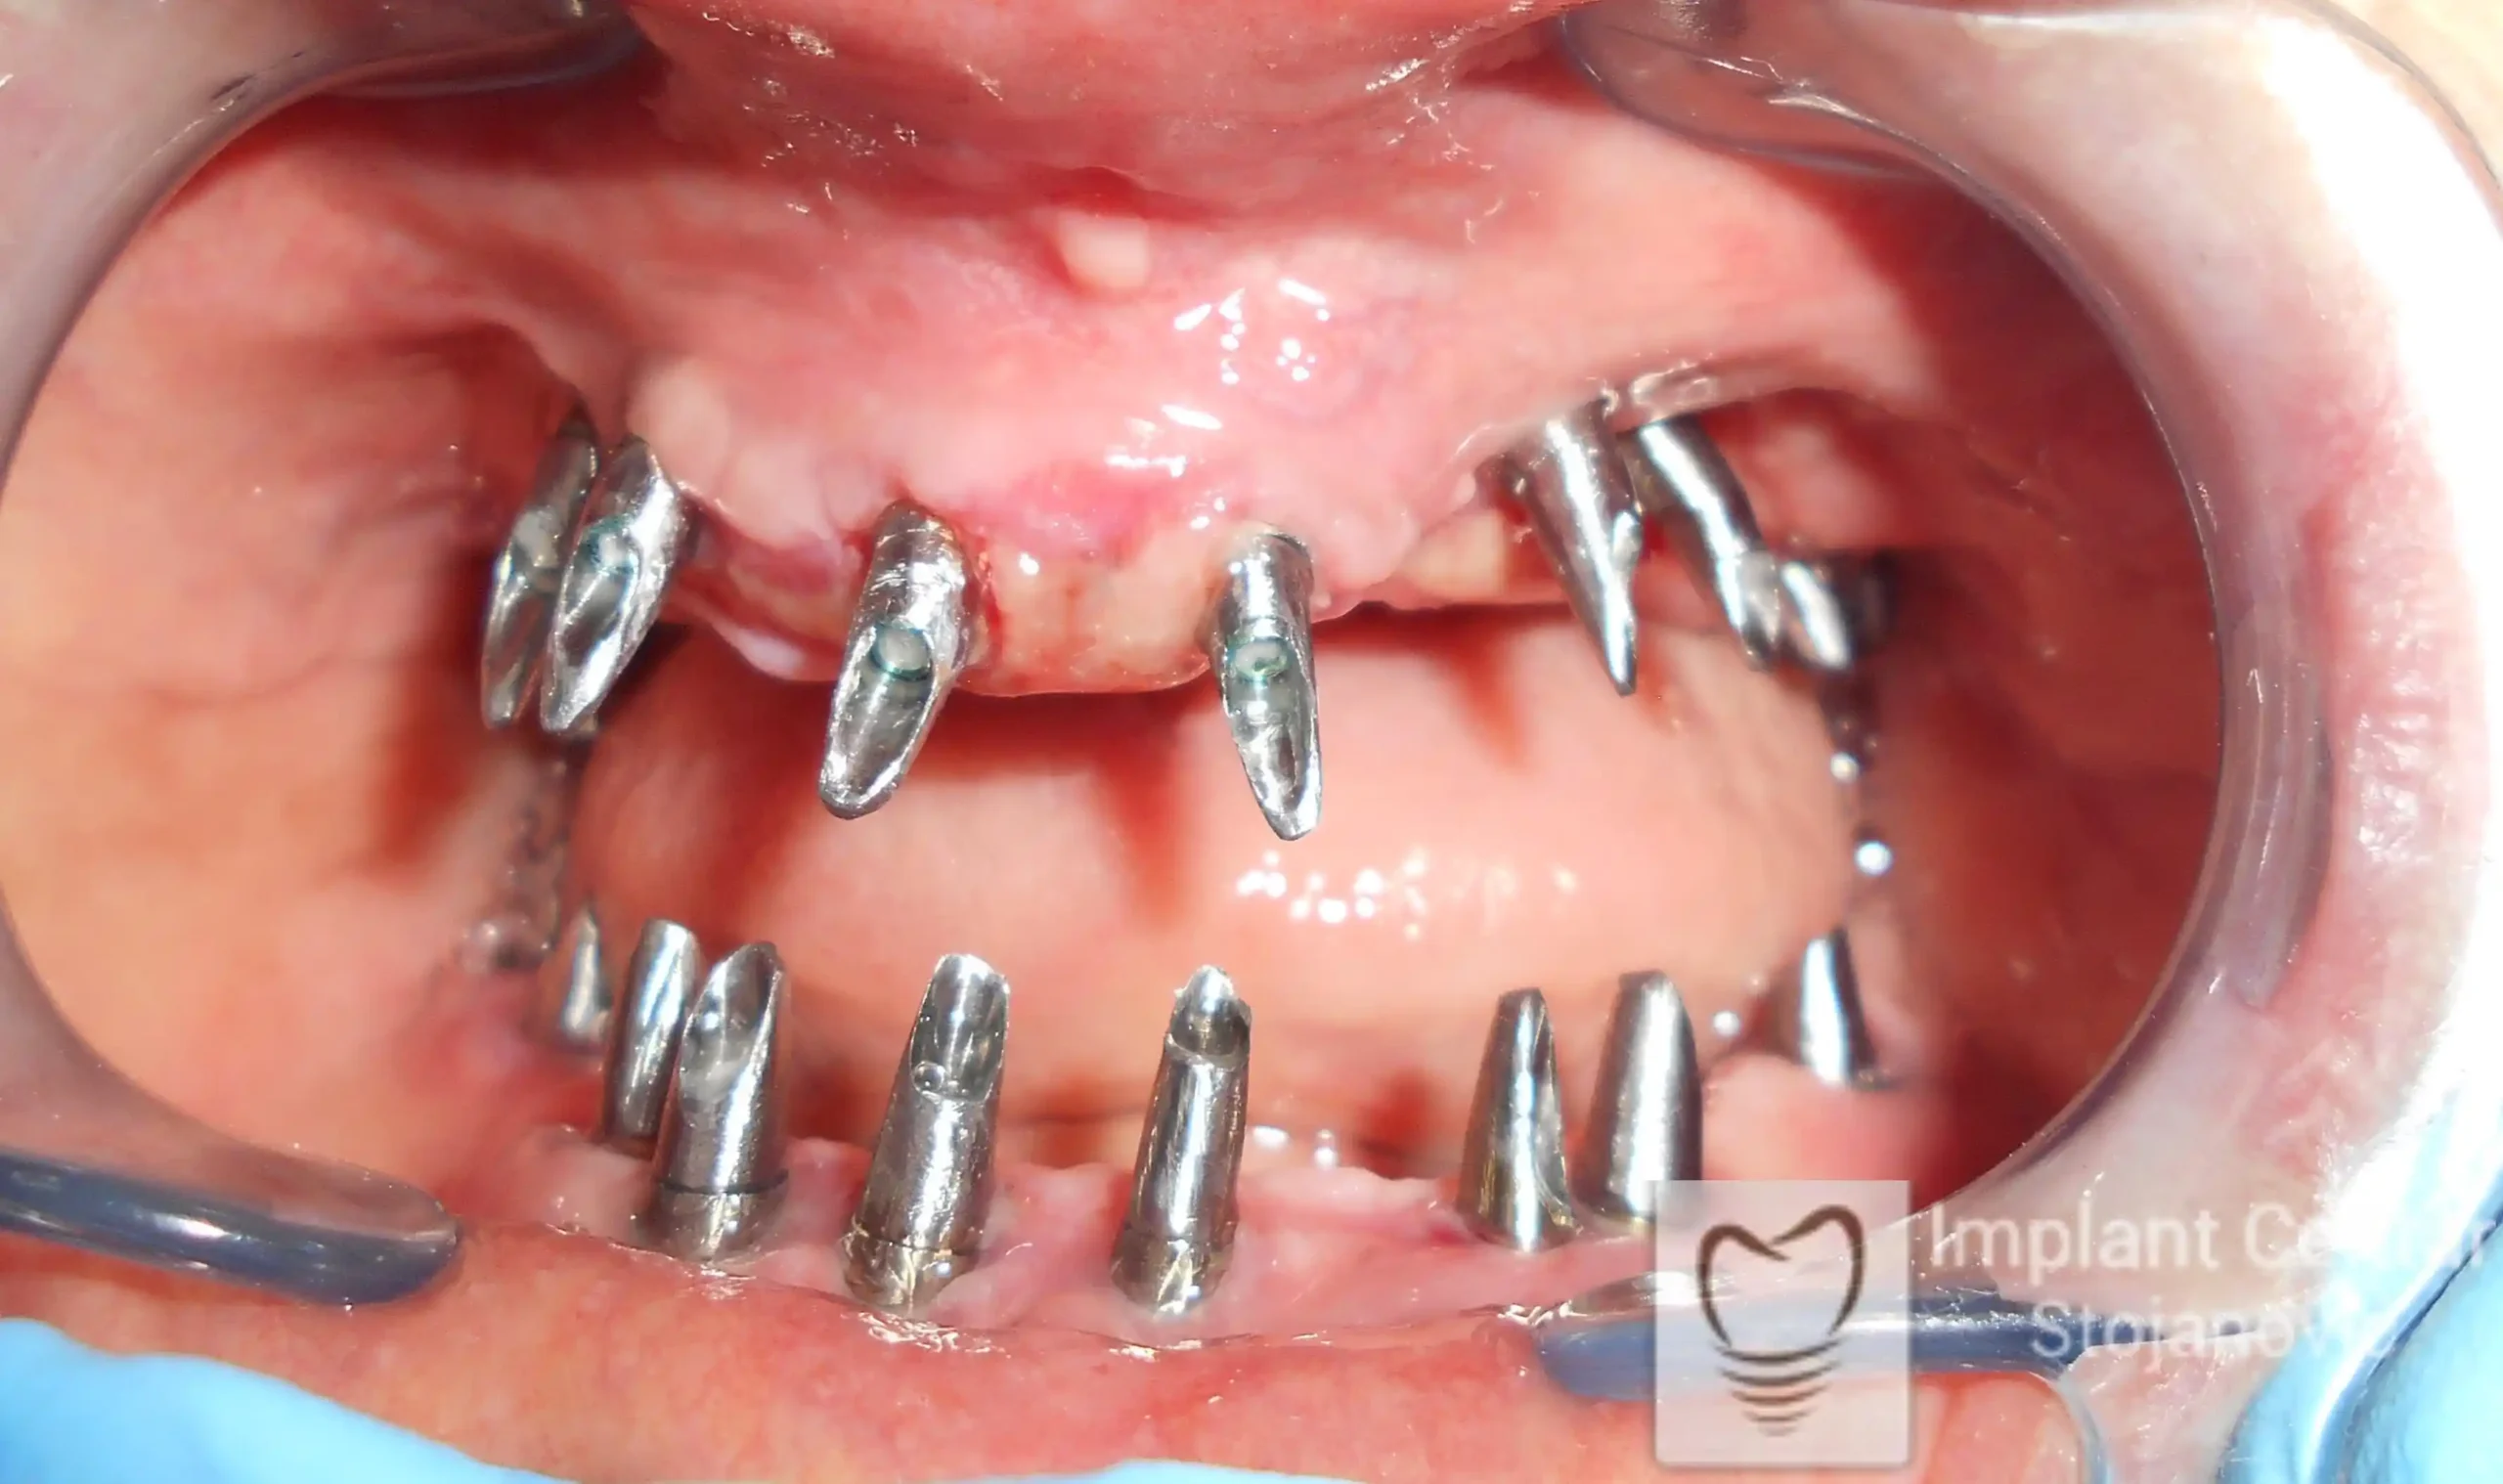

Nakon vađenja zuba, ugrađeni su implantati. Na slici 3 prikazan je ortopan snimak sa ugrđenim implantatima. Tokom perioda osteointegracije, pacijent je bio zbrinut fiksnim privremenim krunicama na implantatima, koje su izrađene samo dva dana nakon hirurške intervencije.

Na slikama 5. i 6. prikazan je izgled definitivnih cirkonijum-keramičkih mostova na implantatima.